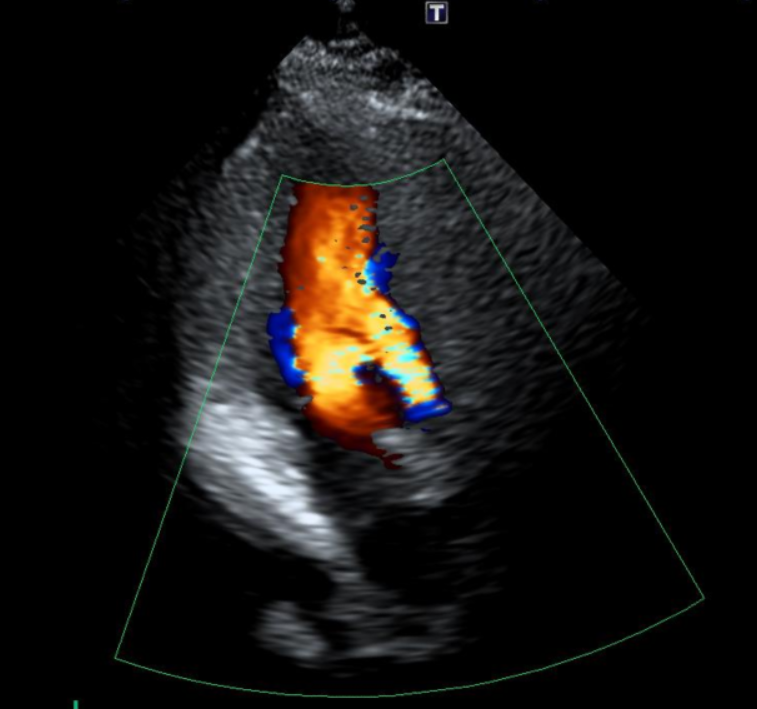

2. 심장초음파

• 심장초음파 검사 결과: 심장판막 2부위에서 승모판막 역류로 인한 폐쇄부전증 확인 심장초음파 검사 결과: 심장판막 2부위에서 승모판막 역류로 인한 폐쇄부전증 확인